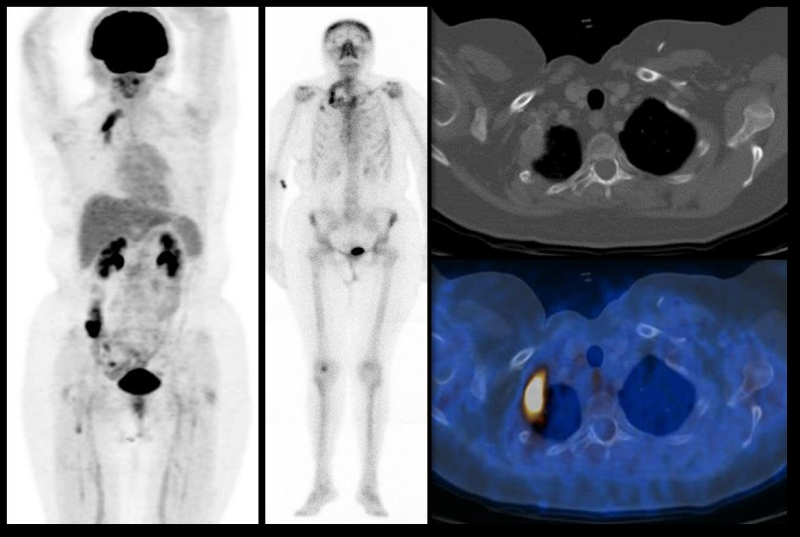

Figura 2.

Figura 2. Paciente de 62 años con historia de cáncer de mama de 20 años de evolución. Derecha, PET-CT con FDG; centro, gammagrama óseo; derecha, cortes transvrsales del CT (arriba) y fusión PET-CT (abajo). Se observa una lesión lítica en el segundo arco costal derecho con intenso incremento en el metabolismo, que muestra además intenso incremento en la actividad osteoneogénica.